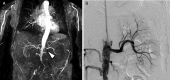

Extracorporeal shock wave lithotripsy (ESWL) for pancreatic stones is considered a safe and efficient method to facilitate fragmentation and stone removal. We describe the case of a 73-year-old woman with a solitary functioning kidney who presented an acute-onset anuria and renovascular renal failure the day after ESWL. We speculate that vascular calcifications in the area targeted by shock waves played a critical role in renal artery obstruction in the present case.